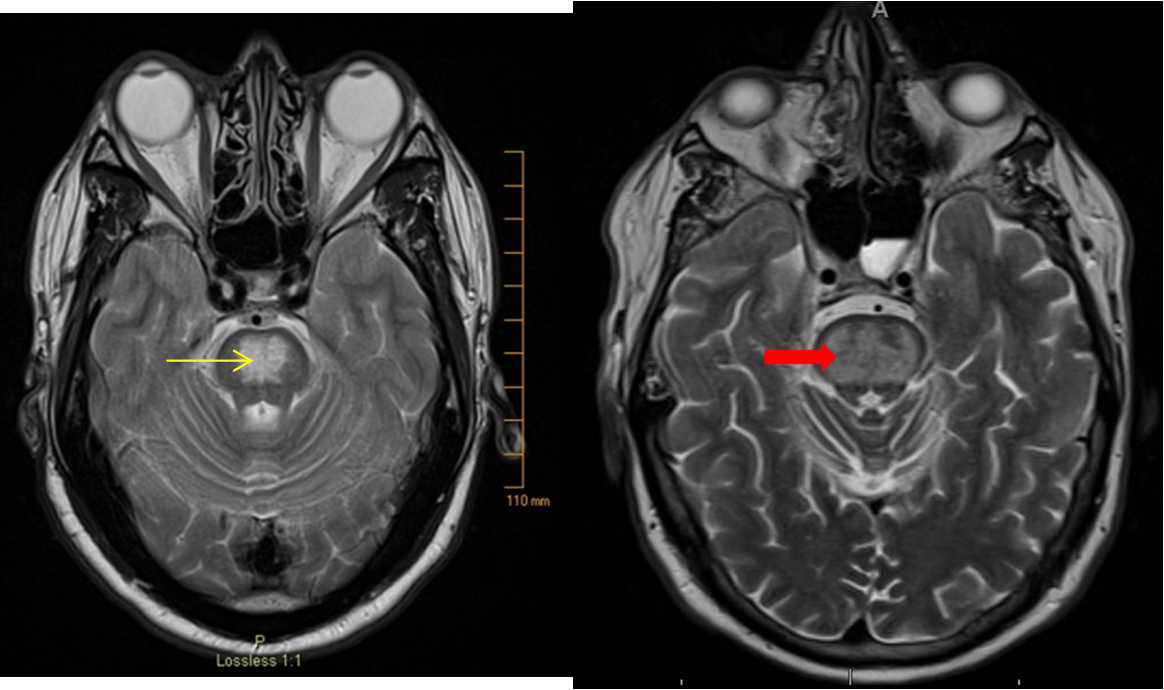

Goal is to avoid a rapid drop of the serum Na+, which is a risk factor for central pontine demyelination and manifests as seizures Z.